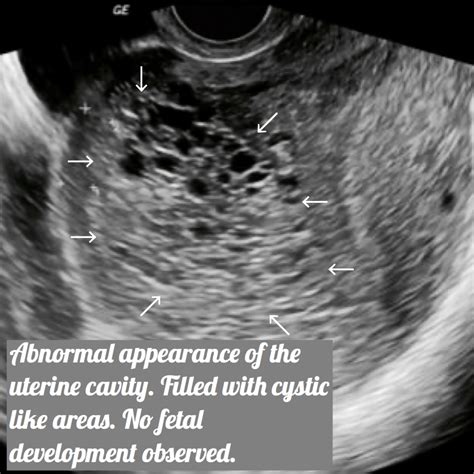

Ultrasound imaging reveals several distinctive features that are indicative of a molar pregnancy. These features include:

• Snowstorm Appearance: This is a classic ultrasound finding in complete molar pregnancies, where the uterus appears filled with small, grapelike cysts.

• Theca Lutein Cysts: These are ovarian cysts that can develop in response to high hCG levels and are often seen in molar pregnancies.

• Absence of Fetal Pole: In complete molar pregnancies, there is no visible fetal pole or yolk sac.

• Partial Molar Pregnancy Features: In partial molar pregnancies, there may be a visible fetal pole, but it is often abnormal, and the placenta shows cystic changes.

These ultrasound features are crucial for differentiating molar pregnancies from other gestational abnormalities.